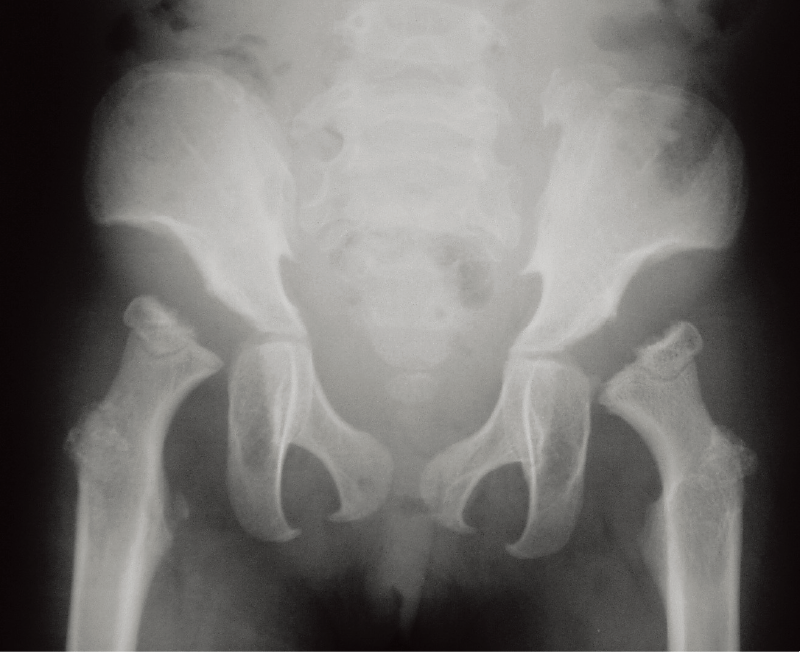

A. 両股関節正面像(8歳、男):腸骨稜のレース様所見と大腿骨頚部の短縮を認める。